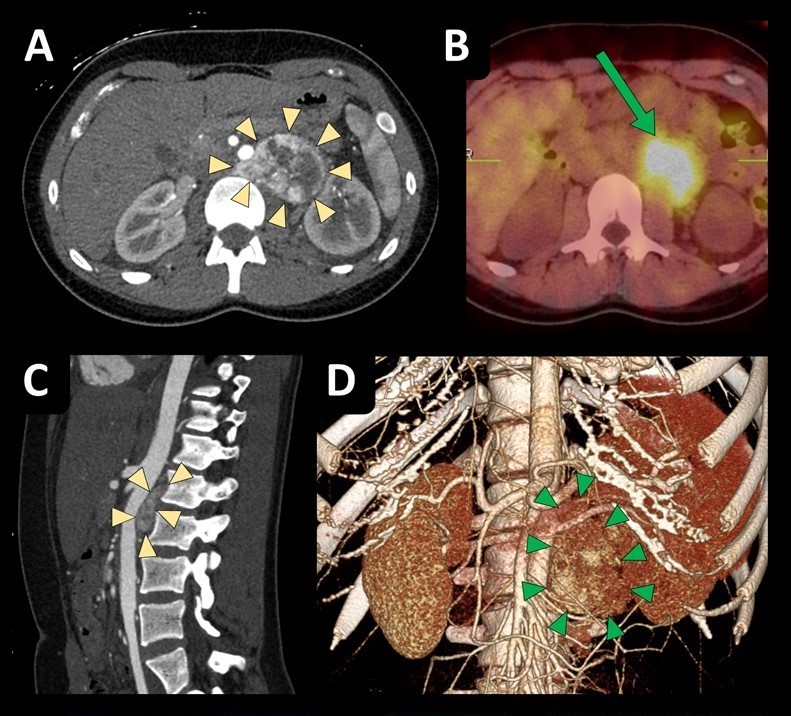

π₯ Thrilled to share my first-ever teaching surgical video in @AnnSurgOncol featuring a complex #robotic resection of paraaortic #paraganglioma and its further management π Kudos to my incredible co-authors @KateBaronMD1, Dr. Wernberg, and Dr. Sharma π https://t.co/H1xKHsYSBM